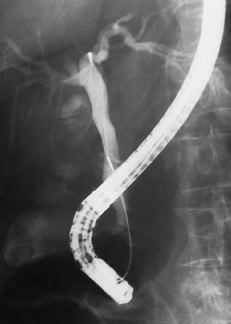

ABCFig. 9.--Páncreas divisum. A) Reconstrucción MIP a partir de secuencia HASTE en proyección coronal; se visualiza el conducto pancreático ventral (flechas) y el conducto pancreático dorsal (punta de flechas) sin conexión de ambos. B) Mismo detalle en un corte axial de una secuencia HASTE. C) En la CPRE sólo se ha opacificado el conducto ventral (flechas).

El páncreas divisum es una anomalía congénita que resulta del fallo de fusión entre páncreas ventral y dorsal durante la sexta-octava semanas de gestación. La prevalencia de esta anomalía en autopsias es del 4-14% (3) y por CPRE es del 2-8% (4). En muchos casos la ausencia de fusión es completa y no existe comunicación entre páncreas ventral y dorsal (Figs. 9A, B y C). También existe una forma incompleta en la que persiste un fino conducto entre ambos, siendo el dorsal predominante (Fig. 10). La importancia clínica del páncreas divisum es controvertida; algunos autores piensan que se trata de una variante de la normalidad y que no tiene relación con pancreatitis (5). Otros autores creen que esta anomalía puede inducir episodios recurrentes de pancreatitis y que éstos se beneficiarían de una esfinterectomía de la papila menor (6).